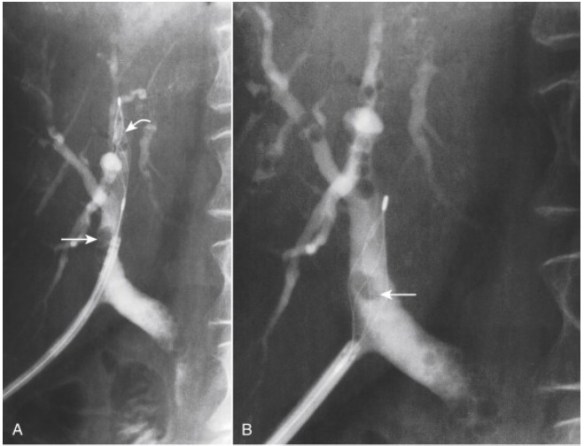

Figure 20-27. Percutaneous extraction of a retained common bile duct stone through a T-tube track. A, The T-tube has been removed and a steerable Burhenne catheter placed through the percutaneous track into the bile duct to the level of the stone (small arrow) . A basket (curved arrow) has been placed distal to the stone. B, The basket is pulled back and manipulated so that the stone (arrow) is engaged within the basket and the basket is then pulled back against the end of the Burhenne catheter. Basket, stone, and Burhenne catheter are then removed through the percutaneous track. C, There is some air present in the lower bile duct. The basket was traversed through the lower bile duct but no further stones were present. Contrast injection at the end of the procedure showed a clear bile duct.